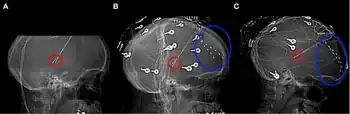

a-c) Thalamic stimulator contacts in red, subdural electrodes in blue.